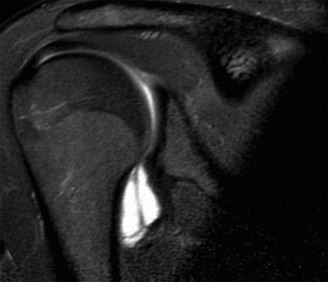

A 45-year-old carpenter presents with shoulder pain that has been ongoing for the last 3 months. He denies any significant injury. He describes night pain and significant discomfort at work. His imaging is shown in Figure 2–9. What is the most likely diagnosis?

Figure 2–9_From Shi LL, Mullen MG, Freehill MT, et al. Accuracy of Long Head of the Biceps Subluxation as a Predictor for Subscapularis Tears. _Arthroscopy 2015;32(4):615–619.

Discussion

The correct answer is (A). Medial subluxation of the biceps tendon as seen in this MRI is commonly associated with a tear of the subscapularis tendon which attaches to the lesser tuberosity. This patient’s pain may in part be attributable to the subscapular tear and this should be evaluated for during physical examination. Supraspinatus tears (Answer B) cannot be easily visualized on axial views and are not associated with medial biceps subluxations. A labral tear and ALPSA lesion (Answers C and D) are not seen on the images provided. The question stem and MRI are not suggestive of shoulder instability (Answer E). Objectives: Did you learn...? Diagnose and treat acute rotator cuff tears?

Which of the following findings is indicative of a subscapularis tendon tear?

Discussion

The answer is (B). As the four layers of the lateral rotator interval insert onto the lesser tuberosity of the humerus, they form the “reflection pulley” that forms a sling around the tendon of the long head of the biceps before it enters the bicipital (intertubercular) groove. A tear of the upper part of the subscapularis can disrupt this reflection pulley and destabilize the biceps tendon, allowing it to sublux or even

dislocate out of its groove, usually in a medial direction. If this happens, the intertubercular groove will be empty on MRI. Often, a “pulley sign” will also be seen on MRI when this occurs. This is when contrast material extravasates extra-articularly just over the superior border of the subscapularis tendon on axial images (see Fig. 2–11).

Figure 2–11_Axial T1 MRI. Left: an empty intertubercular sulcus, positive pulley sign (straight _black arrow on left), and dislocated biceps tendon (curved black arrow). Right: fraying subscapularis tendon (arrow). (From Lyons RP, Green A. Subscapularis tendon tears. J Am Acad Orthop Surg. 2005;13(5):353–363.)